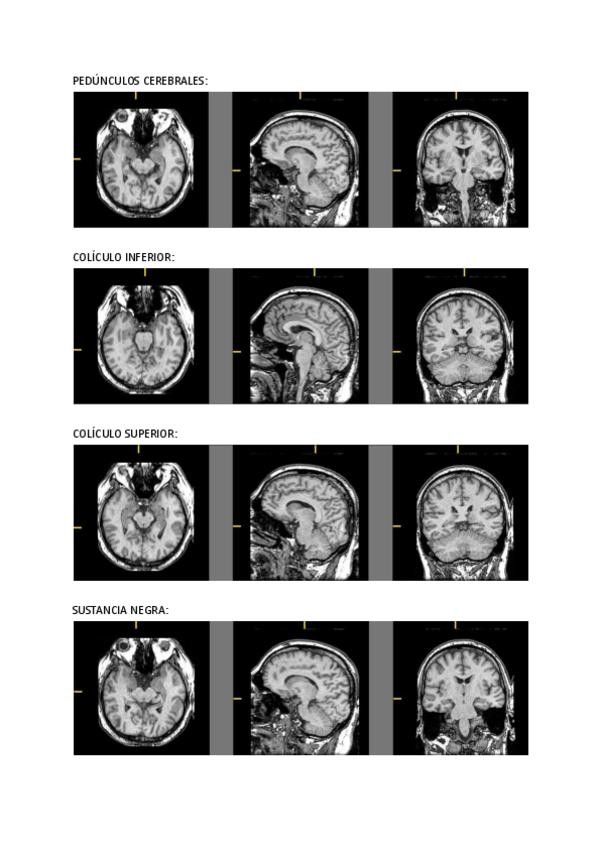

He publicado nuevos apuntes de 1º Fundamentos de Psicobiología Ii: Resonancias-magneticas.pdf

16 páginas